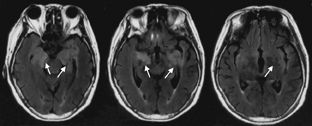

患者女性,72岁,主因渐进性右肢力弱9个月、记忆力减退3个月、错认1周于2015年6月17日入天津市环湖医院。患者于入院前9个月渐感做家务时右手无名指、小指力弱,遂就诊于天津市某综合医院,行头颅CT检查(图1),考虑脑梗死,给予输液治疗2周,此症状渐进性加重,累及中指及右手。于入院前3个月,患者因右手持物力弱、右下肢行走无力、记忆力减退、近期发生过的事情记不起来,再次就诊于天津市某中医医院,行头部MRI检查(图2),FLAIR序列可见双侧颞叶内侧面、海马区高信号影。按照脑梗死给予输液治疗,并口服阿司匹林、阿托伐他汀治疗。于入院前1周,患者右肢无力较前加重,右手持物不稳,右下肢站立及行走需搀扶,并数次跌倒。家属发现其偶有面孔错认,把自己的亲人认错。为进一步诊治收入院。自发病以来,患者无明显头痛及头晕,无视物旋转及视物成双,无恶心呕吐,无耳聋耳鸣,无肢体麻木及抽搐,无意识障碍,存在情绪低落、兴趣减少、食欲下降,体重3个月内减轻5 kg。既往史:有高血压病史20余年,血压最高达160/100 mmHg (1 mmHg=0.133 kPa),平时口服缬沙坦80 mg (1次/d)降压治疗,血压维持在120~130/90 mmHg。入院后神经科体检:意识清楚、构音障碍,双瞳孔等大等圆,光反射(+),眼动可,眼位居中,无眼震及复视,右侧鼻唇沟稍浅,伸舌尚居中,颈软,右肢肌力Ⅳ级,左肢肌力Ⅴ级,肌张力可,腱反射(++),双侧巴宾斯基征(-),右面部及右侧肢体浅感觉异常,双侧共济检查稳准。高级神经活动认知功能检查:简易精神状态检查评分12分,蒙特利尔认知评估量表评分7分,定向力、回忆能力、计算力、语言重复流畅性、执行功能、视空间结构等领域均受累。实验室检查阳性结果:血常规示中性粒细胞百分比83.0%(正常值40%~75%),血小板计数68×109/L[正常值(125~350)×109/L];红细胞沉降率37.00 mm/h(正常值0~15 mm/h),乳酸脱氢酶265 U/L(正常值135~225 U/L];甲状腺功能全项:三碘甲状腺原氨酸1.00 nmol/L(正常值1.3~3.1 nmol/L);血液三项:叶酸4.08 ng/ml(正常值4.6~34.8 ng/ml)。超敏C反应蛋白、乙型肝炎、梅毒血清学检查结果正常。肺癌和肝脏、胃肠、盆腔肿瘤标志物检查结果正常。入院后行腰椎穿刺检查,压力200 mmH2O(1 mmH2O=0.009 8 kPa);脑脊液常规:总细胞数382×106/L,白细胞数2×106/L[正常成人(0~8)×106/L] ;脑脊液生化:氯化物117 mmol/L(正常值120~132 mmol/L],蛋白1.18 g/L(正常值0.15~0.45 g/L),乳酸5.4 mmol/L(正常值0.6~2.2 mmol/L)。脑脊液免疫功能:白蛋白714.00 mg/L(正常值0~350 mg/L),免疫球蛋白A 6.89 mg/L(正常值0.1~5 mg/L),免疫球蛋白G 56.30 mg/L(正常值0.1~34 mg/L),免疫球蛋白M 2.68 mg/L(正常值0~1.3 mg/L)。脑脊液病理检查可见大量红细胞及少量单核细胞、淋巴细胞。入院后查头颅MRI(2015年6月18日;图3)示双侧岛叶、双侧海马FLAIR高信号(较3月前增大)。增强头颅MRI(2015年6月19日;图4)示双侧颞极、双侧海马、双侧岛叶轻度肿胀,伴异常信号,增强后未见明显异常强化。胸片示主动脉硬化,腹部超声示肝胆胰脾未见明显异常。胸部CT、肝胆胰CT未见异常。盆腔CT示双侧附件区点状钙化影,考虑输卵管钙化。泌尿系超声未见明显异常。肌电图提示:右上肢(颈6~8)神经源性损害,重频电刺激未见明显异常。脑电图提示:清醒及睡眠脑电图各导联可见较多散在低中幅不规则慢波,以前头部为著,未见痫样波发放。副肿瘤相关抗体检查:血及脑脊液双份抗Ma2抗体检测,血为阳性(++),脑脊液阴性;抗神经元胞核抗体(Hu-Ri-Yo)、抗塌陷反应调节蛋白5(cV2)抗体、抗双载蛋白(amphiphysin)抗体阴性;N-甲基-D-天冬氨酸(NMDA)受体抗体、谷氨酸α-氨基-3-羟基-5-甲基-4-异